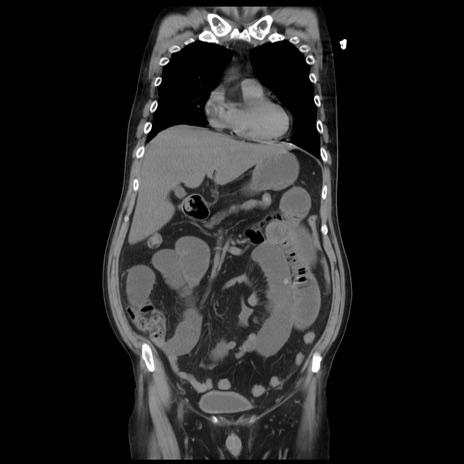

症例20(冠状断像)

【症例】 60歳代男性

【主訴】 腹部膨満、嘔吐

【現病歴】5日前頃より倦怠感を認め食事量減少し4日前の朝嘔吐、食事摂取困難となった。 3日前近医受診し点滴施行され整腸剤などを処方された。 当日他院を受診し、腹部膨満著明、炎症反応の上昇(CRP10.8、WBC11200)あり、紹介受診となる。

【身体所見】 意識JCS1 受け答えがはっきりしないBP 111/57mHg、 P 67bpm、、BT35.2°C、SpO2 97%(RA)、 腹部:膨隆、打診で鼓音あり、全体的に圧痛有り、腸蠕動音(-)、反跳痛ははっきりせず。

【データ】WBC 11400、CRP 14.20